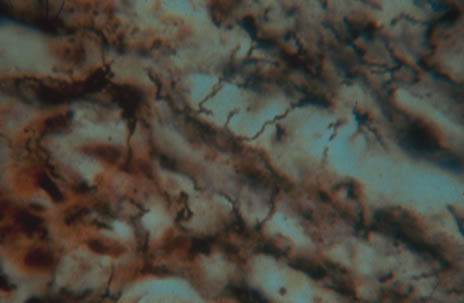

Any cell type may be infected, appearing larger than normal (cytomegalic) and demonstrating eosinophilic intranuclear “owl's eye” and smaller intracytoplasmic viral inclusion bodies, which are better seen with Giemsa or Papanicolaou's stains (Fig. 8). Histologic examination of tissue specimens, including bronchoalveolar lavage fluid and urine, may be useful for diagnosis.

Fig. 8. Typical lesion of cytomegalovirus (CMV) produces retinal necrosis with large cells possessing owl's eye inclusions.